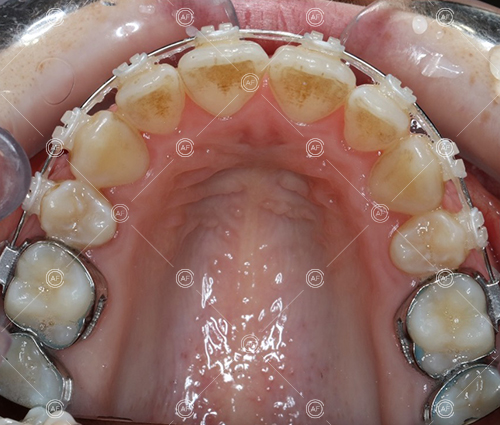

Treatment progressed by starting with thin, flexible nickel titanium archwires of a round diameter, transitioning to a rectangular nickel titanium archwire before eventually working up to a working archwire (1925 stainless steel).

Residual space from the extractions were closed using upper and lower nickel titanium closing coils. Class 2 elastics were used to facilitate space closure in order to gain class 1 buccal segments.